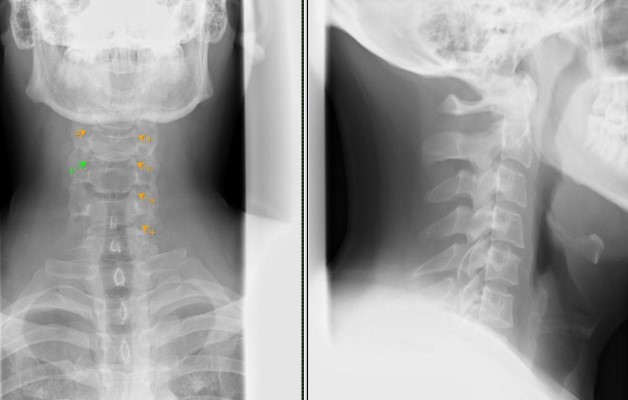

Как выглядит артроз на рентгене

Рентгенологическое исследование используется при диагностике заболевания. На снимке отчетливо видны патологические изменения, которые происходят с телами шейных позвонков:

- сегменты утолщаются и уплощаются, разрастаясь в стороны;

- происходит уменьшение хрящевой ткани;

- появляются остеофиты, острые отростки, которые спазмируют нервные окончания и кровеносные сосуды;

- спинномозговой канал и щель между позвонками сужаются.

На заметку. Хирург-ортопед, изучая рентген, в первую очередь обратит внимание на размер позвонков. Если они увеличены, есть все основания подозревать у человека артроз.